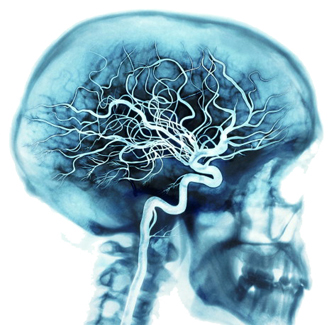

2. Aivojen ravitsemus

Aivojesi ravitsemuksesta huolehtii yksi elimist�si tiheimmist� verisuoniverkostoista.

Jokaisella syd�men ly�nnill� valtimot kuljettavat noin 20 - 25 prosenttia elimist�ss�si virtaavasta verest� aivoihin, miss� miljardit solut hy�dynt�v�t 20 prosenttia kaikesta veren kuljettamasta hapesta ja ravinteista.

Rankassa ajatteluty�ss� aivot voivat k�ytt�� jopa 50 prosenttia verenkierron kautta tulevasta hapesta ja ravinteista.

Koko verisuoniverkostosi k�sitt�� valtimoiden lis�ksi laskimoita ja hiussuonia.